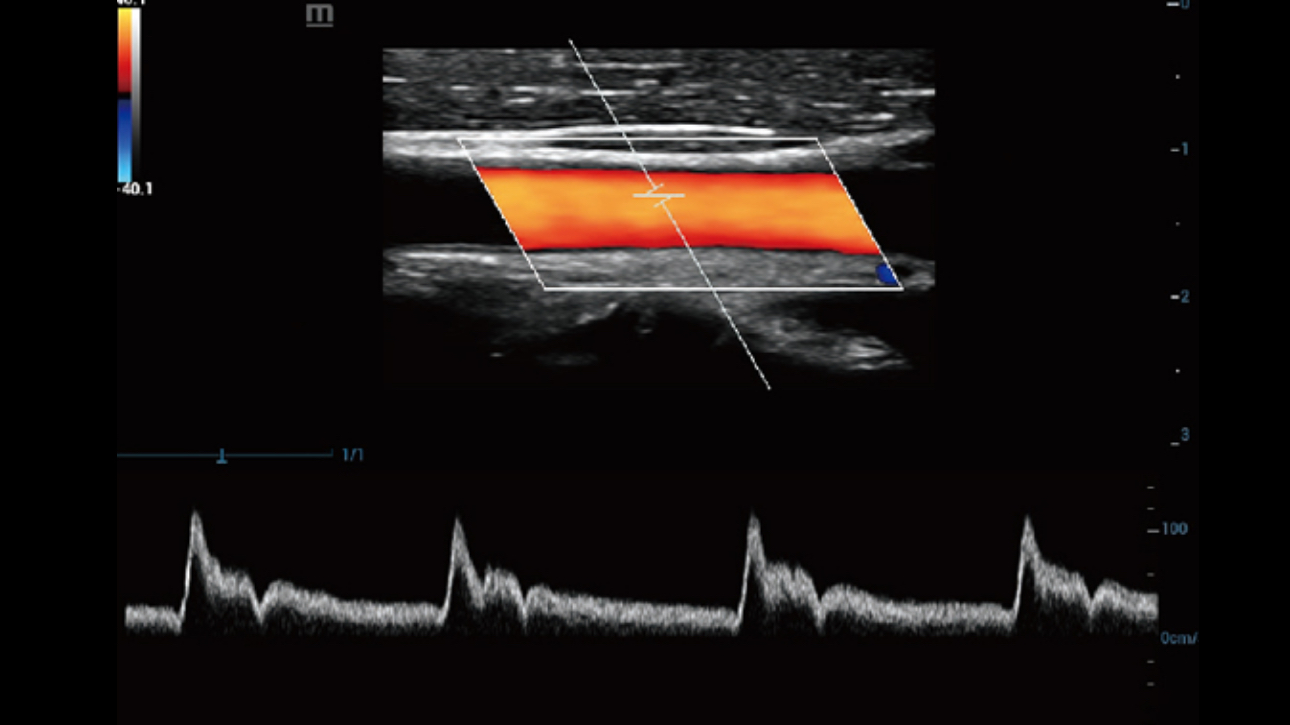

Dynamic Pixel Focusing technology allows the Resona 6 to achieve extreme uniformity in pixel level throughout the whole field of view. Now there's no need to adjust the focal positions to achieve uniformity across patient exams.

Channel data based ZST+ provides Enhanced Channel Data Processing for greatly improved imaging clarity. By multiple and retrospective channel data processing, it makes the best use of acoustic information for image improvement.

HD Scope: By processing channel data retrospectively, HD Scope enables tissue-specific enhancement with improved detailed information and image contrast on specific region of interest.